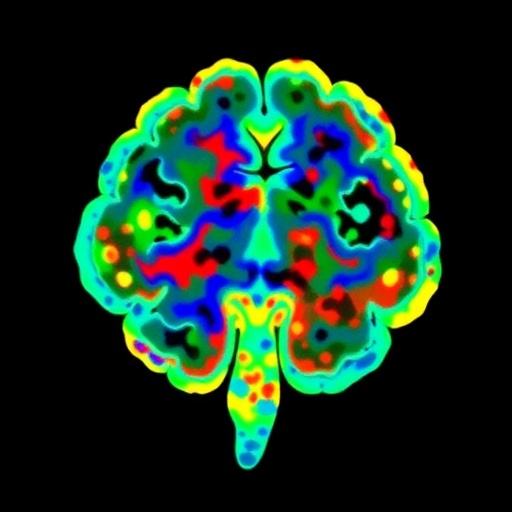

In this study, spearheaded by Habich, Baumann, Schwarz, and their colleagues, researchers employed imaging transcriptomics, a cutting-edge methodological framework that combines neuroimaging data with transcriptome maps. This approach helps pinpoint the locational alignment of gene expression patterns with observed cortical thinning and subcortical atrophy in DLB patients. By cross-referencing large-scale transcriptomic databases with structural MRI scans, the team delineated gene-brain atrophy correlations that shed light on region-specific susceptibilities.

One of the pivotal discoveries demonstrated that distinct clusters of genes involved in synaptic function, lysosomal activity, and proteostasis align spatially with regions exhibiting significant atrophic changes. Notably, genes implicated in alpha-synuclein metabolism—a hallmark protein aggregate in DLB—showed enriched expression within atrophy-prone areas. This reinforces the pathological relevance of alpha-synuclein’s misprocessing and accumulation in shaping neurodegenerative trajectories.

A highlight of the research involves the identification of regionally selective vulnerability that could explain the clinical heterogeneity observed among DLB patients. By mapping transcriptomic landscapes onto atrophic patterns, investigators uncovered genetic profiles unique to vulnerable subcortical nuclei and cortical regions governing cognition and motor control. This granular insight paves the way for tailored interventions targeting region-specific molecular pathways.

Technological breakthroughs in multi-modal data integration underpinned the success of the study. High-resolution magnetic resonance imaging furnished precise quantifications of gray matter volume reductions, while publicly accessible brain transcriptome atlases enabled comprehensive gene expression mapping. Sophisticated bioinformatics pipelines coupled these datasets, allowing robust statistical inference while mitigating confounding factors such as age-related changes and comorbidities.